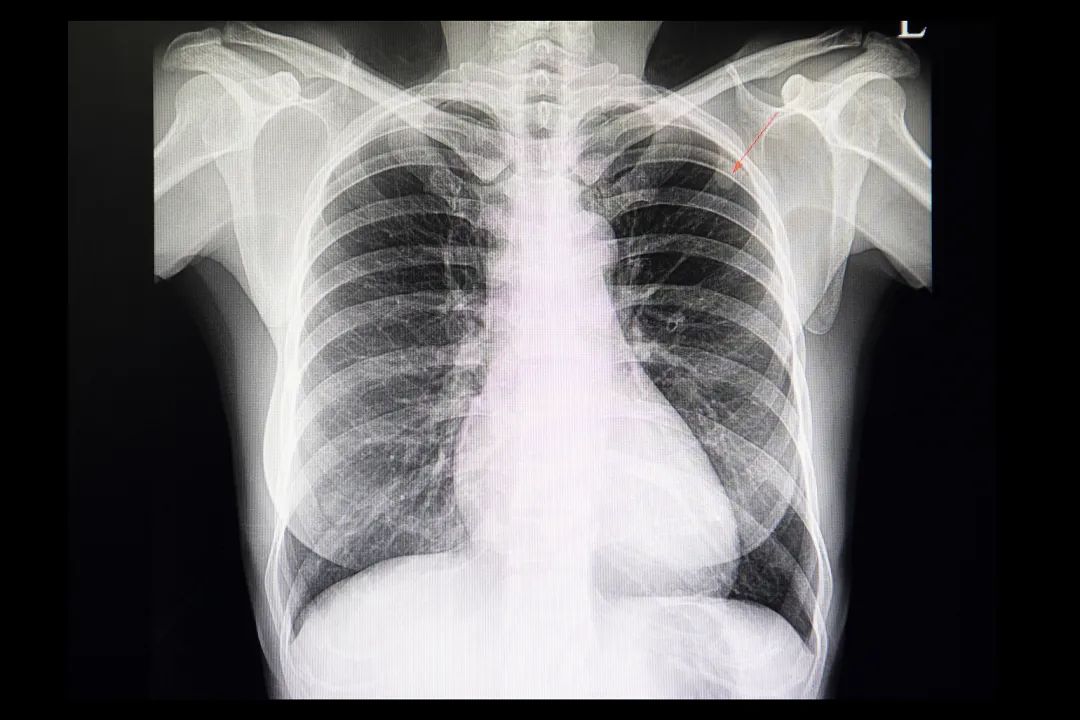

05 看密度[1]

肺结节的恶性概率与其密度有关,其中以部分实性结节的恶性概率最高。结节中实性部分具有侵袭性,实性成分的增加往往代表病灶发生了浸润进展。

06 看外观[1][4]

恶性结节多呈分叶状,边缘大多清楚但并不光整。如果出现毛刺征(或称棘状突起)、胸膜凹陷征及血管集束征常提示结节为恶性的可能性大。

07 看内部结构[1]

肺结节中钙化可表现为中心性、弥漫性、层状、点状、偏心和爆米花样。

其中,病变呈点状、偏心钙化时,结节为恶性的可能性大。